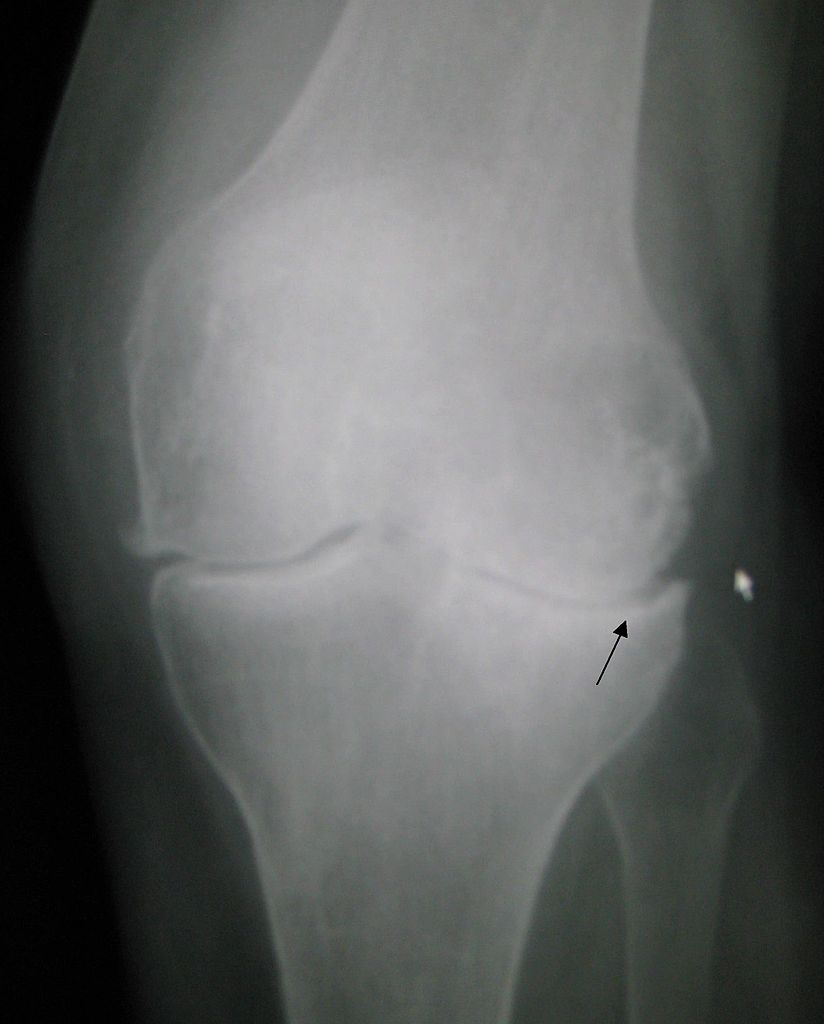

Osteoartritis de rodilla / Knee osteoarthritis

Osteoartritis de rodilla*

Knee osteoarthritis*

Es una inflamación de la articulación de la rodilla. Si se tiene osteoartritis, el cartílago articular se va erosionando gradualmente y se hace más fino.

Osteoarthritis, commonly known as wear-and-tear arthritis, is a condition in which the natural cushioning between joints — cartilage — wears away. When this happens, the bones of the joints rub more closely against one another with less of the shock-absorbing benefits of cartilage. The rubbing results in pain, swelling, stiffness, decreased ability to move and, sometimes, the formation of bone spurs.